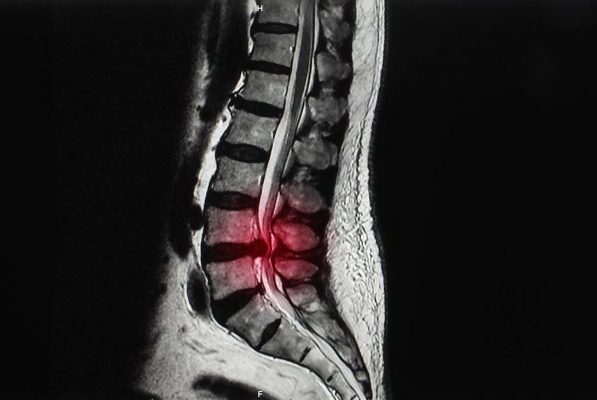

تنگی کانال نخاعی وضعیتی است که با باریک شدن کانال نخاعی مشخص می شود که بر نخاع و اعصاب فشار وارد می کند. این باریک شدن می تواند در گردن (تنگی ستون فقرات گردنی) یا کمر (تنگی ستون فقرات کمری) رخ دهد. شایع ترین علل تنگی کانال نخاعی عبارتند از:

• فتق دیسک: وقتی هسته داخلی دیسک ستون فقرات بیرون زده و روی کانال نخاعی فشار می آورد، می تواند باعث تنگی شود.

درمان تنگی کانال نخاع با فیزیوتراپی

فیزیوتراپی می تواند نقش مهمی در درمان تنگی کانال نخاعی با کمک به تسکین علائم، بهبود عملکرد و افزایش کیفیت کلی زندگی داشته باشد. در اینجا چند راه وجود دارد که فیزیوتراپی می تواند مفید باشد: